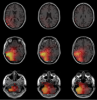

DIPFIT is an EEGLAB plugin to perform inverse source localization.

A major obstacle to using EEG data to visualize macroscopic brain dynamics is the underdetermined nature of the inverse problem: Given an EEG scalp distribution of activity observed at given scalp electrodes, any number of brain source activity distributions can be found that would produce it. This is because there is any number of possible brain source area pairs or etc. that, jointly, add to the scalp data. Therefore, solving this EEG inverse problem requires making additional assumptions about the nature of the source distributions. A computationally tractable approach is to find some number of brain current dipoles (like vanishingly small batteries) whose summed projections to the scalp most nearly resemble the observed scalp distribution.